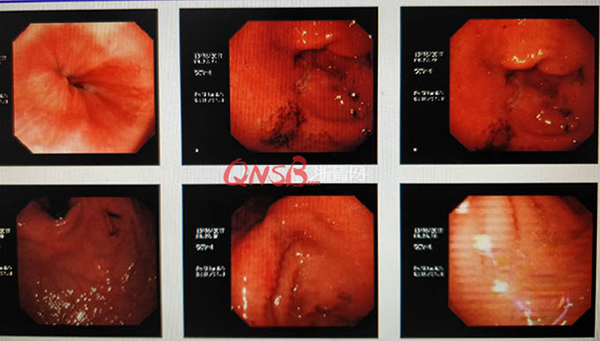

檢查結(jié)果出來后,小周大吃一驚,本以為自己的胃很健康,卻不想胃粘膜廣泛充血糜爛,長(zhǎng)了兩個(gè)巨大的潰瘍(直徑大于2厘米),還有出血和咖啡色血痂。